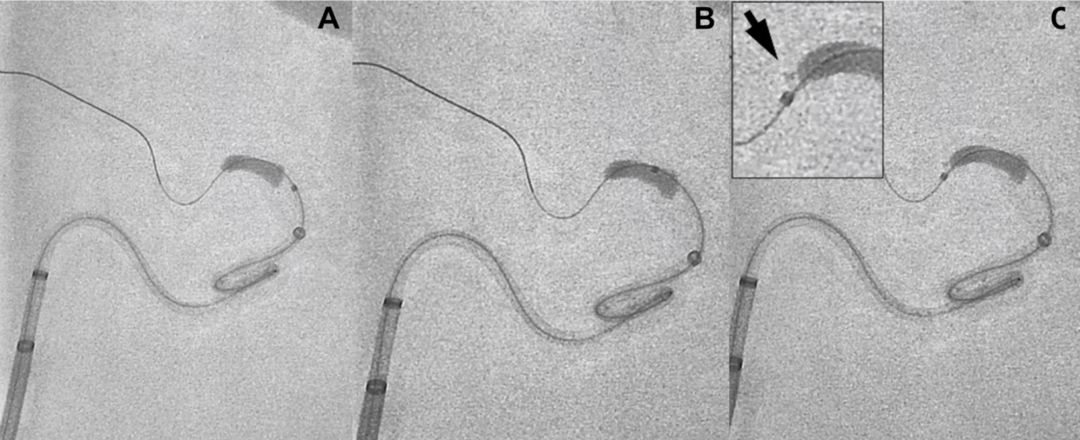

图1:微导管穿越血栓,随后撤出导丝,使用300ml盐水缓慢冲洗微导管收集血栓残片(箭头)

该研究制作了可视化的大脑中动脉血栓模型,并利用3种不同尺寸的微导管(Pro18、XT-27、3MAX)穿越血栓来模拟取栓过程。血栓为通过凝血酶诱导产生的牛血血栓,长度、直径分别为6mm、4.3mm。

首先,采用Synchro-14导引导丝穿越血栓团块,然后,通过不同外径的微导管:Trevo Pro18(OD=2.4F)、Excelsior XT-27(OD=2.7F)、3MAX(OD=3.8F),每种尺寸的微导管重复试验9次。